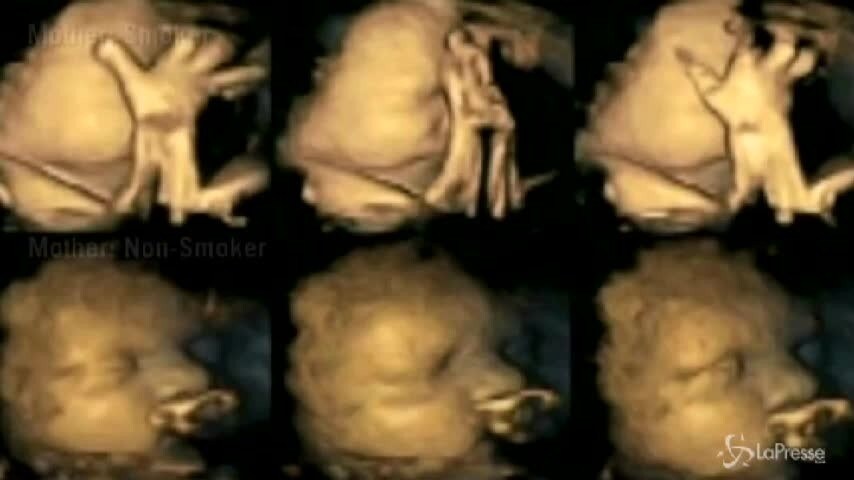

Quanto fa male il fumo al feto

La nozione era già nota, ma una ricercatrice britannica ha deciso di condurre uno studio su 20 donne incinte, di cui quattro sono regolari fumatrici. La ricerca produrrà un video che mostrerà i ritardi di sviluppo e le sofferenze per gli embrioni delle donne fumatrici. In questo modo si spera di convincere le donne a rinunciare alla nicotina almeno durante il periodo della gestazione e dell'allattamento.